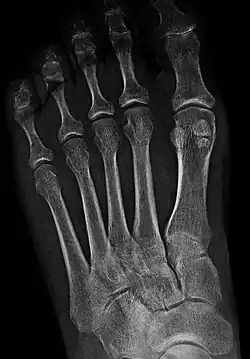

- In the foot—the first metatarsal bone usually has two sesamoid bones at its connection to the big toe (both within the tendon of flexor hallucis brevis).[10] One is found on the lateral side of the first metatarsal while the other is found on the medial side. In some people, only a single sesamoid is found on the first metatarsal bone.

- One or both of the sesamoid bones under the first metatarsophalangeal joint (of the great toe) can be multipartite – in two or three parts (mostly bipartite – in two parts).[12]

Bipartite medial sesamoid bone under the first metatarsophalangeal joint of the great toe of the left foot of an adult woman.